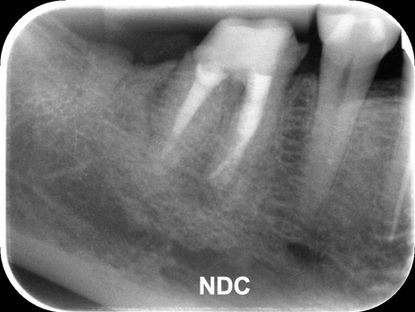

この根尖部の骨吸収は、レントゲン写真では「根の先の影」として見えることになります。

レントゲン写真は歯と骨をフィルムの方向に重ね合わせて平面として捉えることになります。X線が遮られずにたくさんフィルムに到達すれば画像は黒くなります。逆に金属や骨などに遮られてフィルムに少ししか到達しなければ画像は白くなります。つまりフィルムに到達したX線の量によって白黒の濃淡が発生することになります。

根尖性歯周炎によって発生した骨吸収により、その部分は周囲よりも骨の厚みが薄いことになります。したがって周囲よりもX線が透過しやすくなってフィルムに多く届くことで、周囲よりも黒く写ることになります。

これが「根の先の影」が見えるようになるメカニズムです。